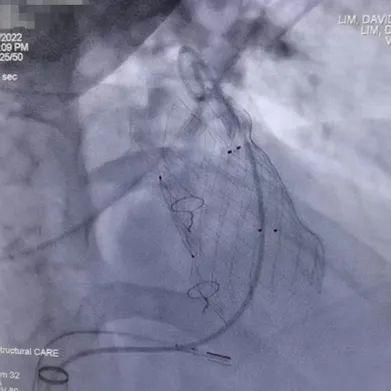

患者是一名21岁青年男性,既往行法洛氏四联症外科跨瓣补片修复术,患有重度肺动脉瓣反流且有显著的右心室、肺动脉扩张及左心室功能障碍。介入手术采用局部麻醉方式,患者清醒状态下穿刺右侧股静脉作为主入路,术中进行了造影及球囊测量,经中美2个团队的再次在线讨论,结合术前CT分析结果,最终精准的选用P34-25(瓣膜腰部直径34mm,长度25mm) VenusP-Valve瓣膜完成植入,即刻造影和超声综合评估显示瓣膜植入位置完美,无反流及残余压差,左右肺动脉分支血流未受影响。术后Scott Lim教授与冯沅教授就手术过程再次进行了讨论,并分享了植入体会。次日好消息传来,超声检查示右室明显变小,无任何肺动脉瓣反流,左室功能恢复正常。术后患者恢复迅速,无并发症发生,患者于术后24小时内,当地时间6月18日出院。

瓣膜植入过程

瓣膜最终植入效果